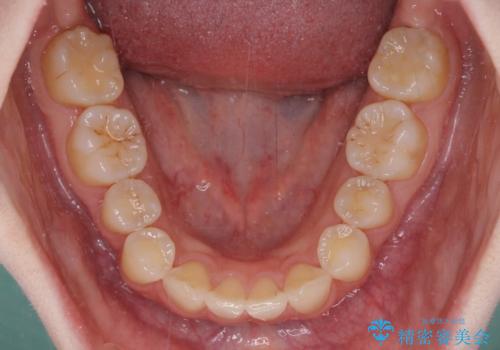

- 上顎前歯の突出感を気にして来院された患者様です。

下顎前歯2本が先天欠損しており、上顎歯列に対して、下顎歯列がアンバランスに小さい状況でした。

左右上顎側切歯2本が矮小歯であるため、上顎の抜歯ではなく、IPR(歯と歯の間を削る)と歯列全体の後方移動によってバランスを整えることとしました。

歯列のバランスが悪く、インビザライン矯正特有の奥歯の噛みにくさがなかなか改善されず、治療期間が長期化してしまいました。